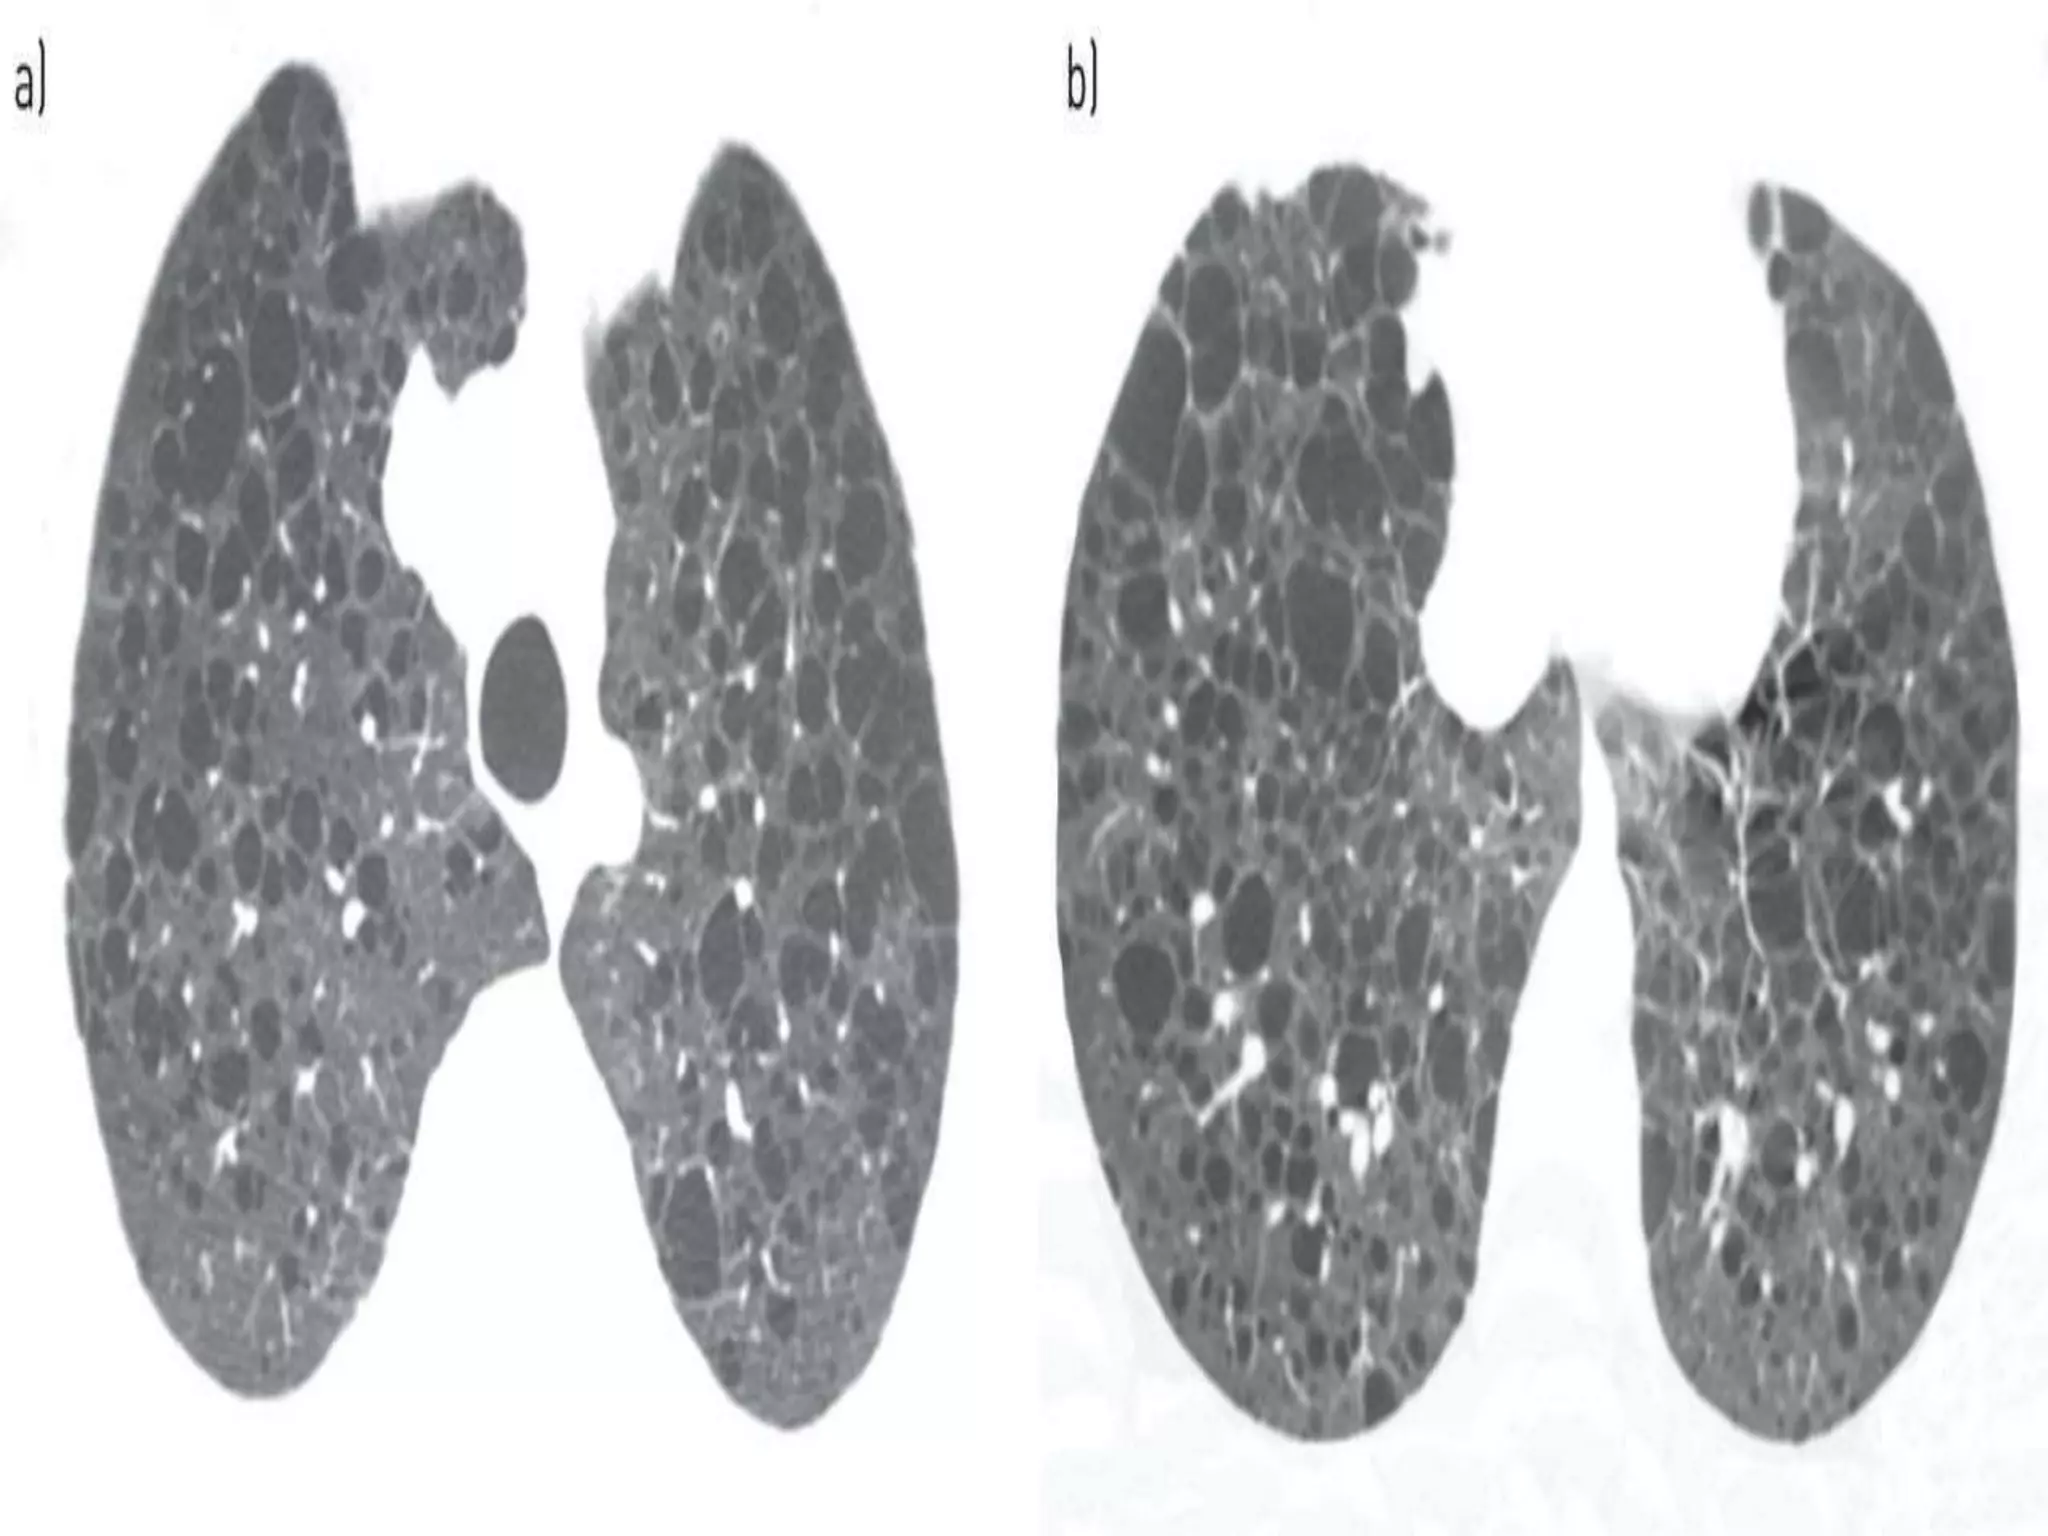

| Multiple fibrofolliculomas on the face of a BHD patient

(arrows). b | Haematoxylin and eosin staining of a

fibrofolliculoma showing strands of epithelial cells surrounded

by fibrous stroma (arrow) with adjacent hair follicle; ×4

magnification. c,d | Chest CT scans of patients with BHD

showing bilateral multiple pulmonary cysts of various sizes

(arrows). Images for panels a and b are provided courtesy of

Dr Mary Eid and Dr Edward Cowen, Dermatology Branch,

National Cancer Institute, National Institutes of Health.

•HRCT finding:

•multiple thin- wall cysts in

>80 % of patients

•These cysts are

predominantly seen in

peripheral lung zones at

lung bases, along

mediastinum and along

pulomnary vein.

•pneumothorax in 24% of

patients.